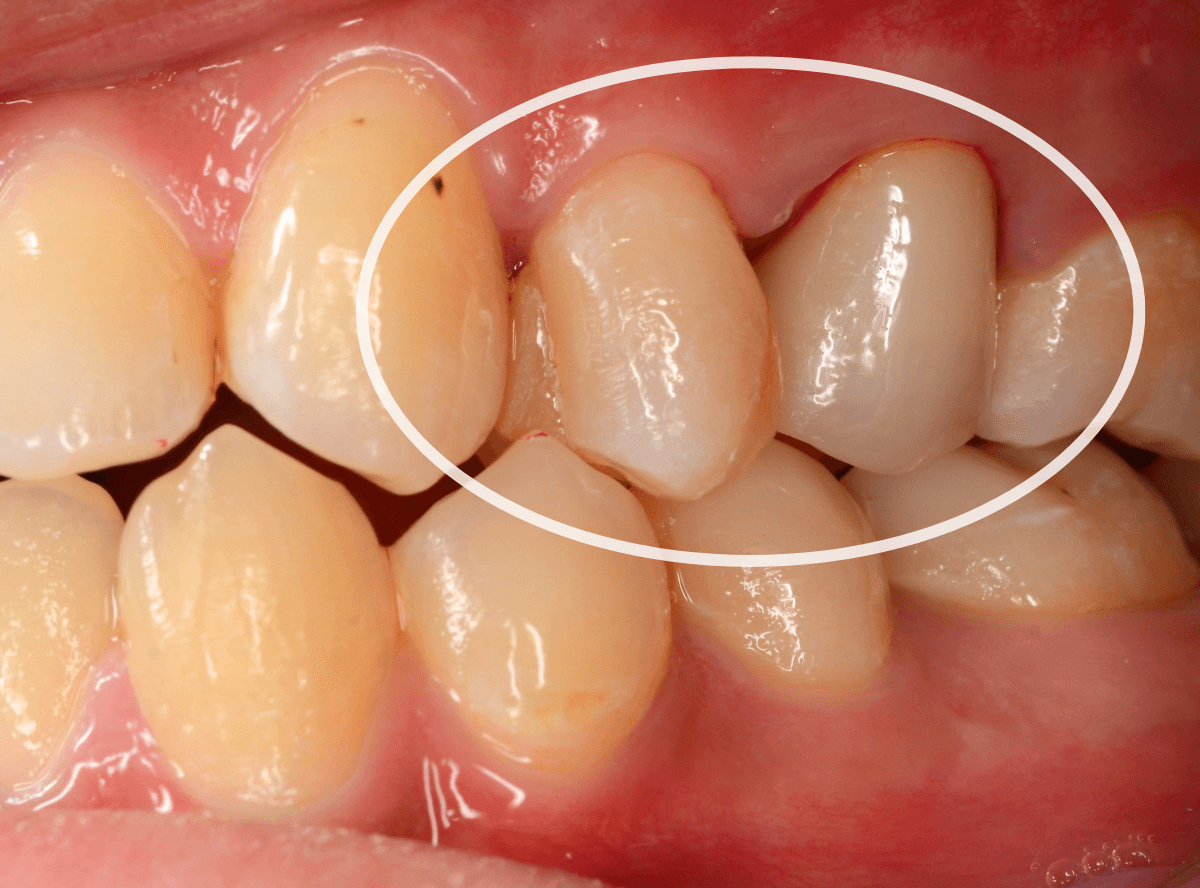

Case.10

さし歯を入れるスペースがない!

一番奥の歯が土台(コア)の治療までで中断してしまってる患者さんの例です。

本来であれば、この上にさし歯を作らなければいけないのですが、この時点でかみ合ってしまい、さし歯を作ろうにも作りづらい状況でうやむやのうちに治療中断になってしまったようです。

まず、土台の治療をしてから時間が経過していることと、不適合になっている事から、外して中を調べます。

すると、土台の中で虫歯にもなっていました。

(〇部の赤い部分)

こういった事は、レントゲン写真でもよくわからない事が多く、土台を外す治療は本当に神経を使います。